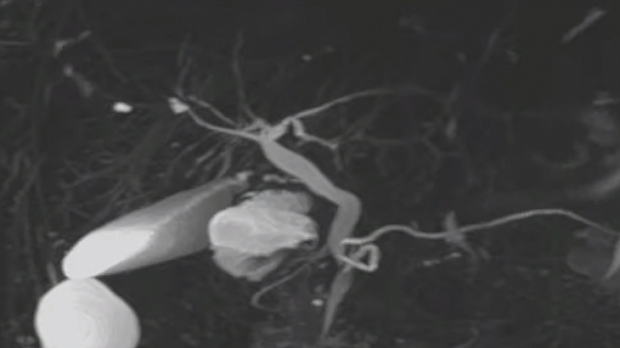

Ответ: кольцевидная поджелудочная железа - "circular pancreas" - это эмбриологический порок развития, характеризующийся наличием кольца ткани поджелудочной железы, полностью или частично окружающего нисходящую (D2 вторую часть) двенадцатиперстной кишки. Его основным клиническим симптомом является полная или частичная дуоденальная непроходимость.

Чаще кольцевидная ПЖ представляет собой неопасный вид аномального развития железы, который или не причиняет особых беспокойств больному, или при достаточно выраженном стенозе, относительно просто корригируется оперативным пособием. В то же время кольцевидная ПЖ примерно в 30 % случаев сочетается с другими аномалиями развития органов желудочно-кишечного тракта, а в ряде случаев — других органов и систем. Эта аномалия может быть частью сложных комбинированных дефектов развития, в том числе и не совместимых с жизнью. Если рассматривать более часто встречающиеся случаи, когда pancreas annulare является изолированным пороком развития, то ее клинические проявления во многом определяются степенью сдавления двенадцатиперстной кишки и нарушением ее проходимости.